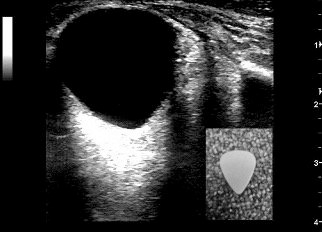

What bedside exam can help confirm the diagnosis of retrobulbar hematoma? Gepost op 25 juni 2018 door netwerkvsseh Blunt Ocular Trauma @emergencymedicinecases.com Dit delen: Delen op X (Opent in een nieuw venster) X Share op Facebook (Opent in een nieuw venster) Facebook Delen op LinkedIn (Opent in een nieuw venster) LinkedIn E-mail een link naar een vriend (Opent in een nieuw venster) E-mail Afdrukken (Opent in een nieuw venster) Print Vind-ik-leuk Aan het laden... Gerelateerd